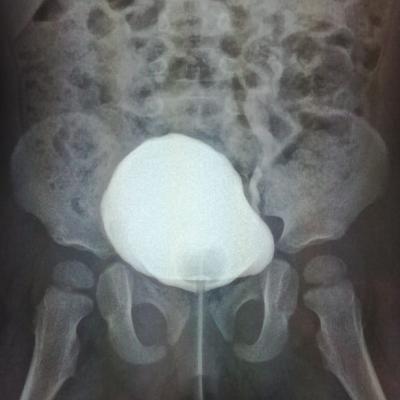

ПМР 4 степени

Здравствуйте.Моему ребенку 14.09.17г.р.была сделана вторая эндоскопическая коррекция ПМР 4 ст. в академии педиатрии СПб 07.06.19,(хотя рекомендовали и квоту одобрили на сложную операцию).08.06.19нас выписали.11.06.19г. ОАМ -удельный вес 1.006; лейкоциты 500(654,9); бактерии 13117,9;мочиться стала ещё реже 3 раза в день.17.06.19 были на приеме у нефролога,кот.нас направил обратно к урологам Академии педиатрии.Зав.отд.,посмотрев ОАМ и выписку ,спросил что я от него хочу...что ОАМ ещё ни о чем не говорит.Назначил прием Фурагина 3 раза в день по 50 мг в теч.месяца.А Вы как считаете,что лучше при такой степени рефлюкса,если почки уже страдают.